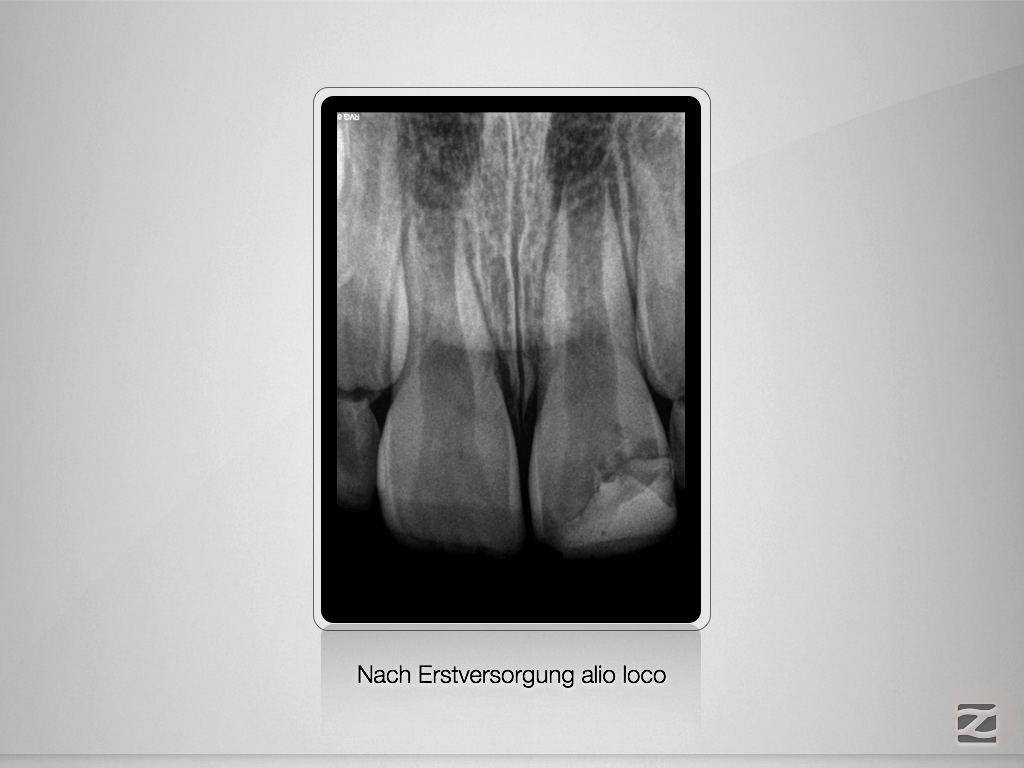

Chance Pulpotomie